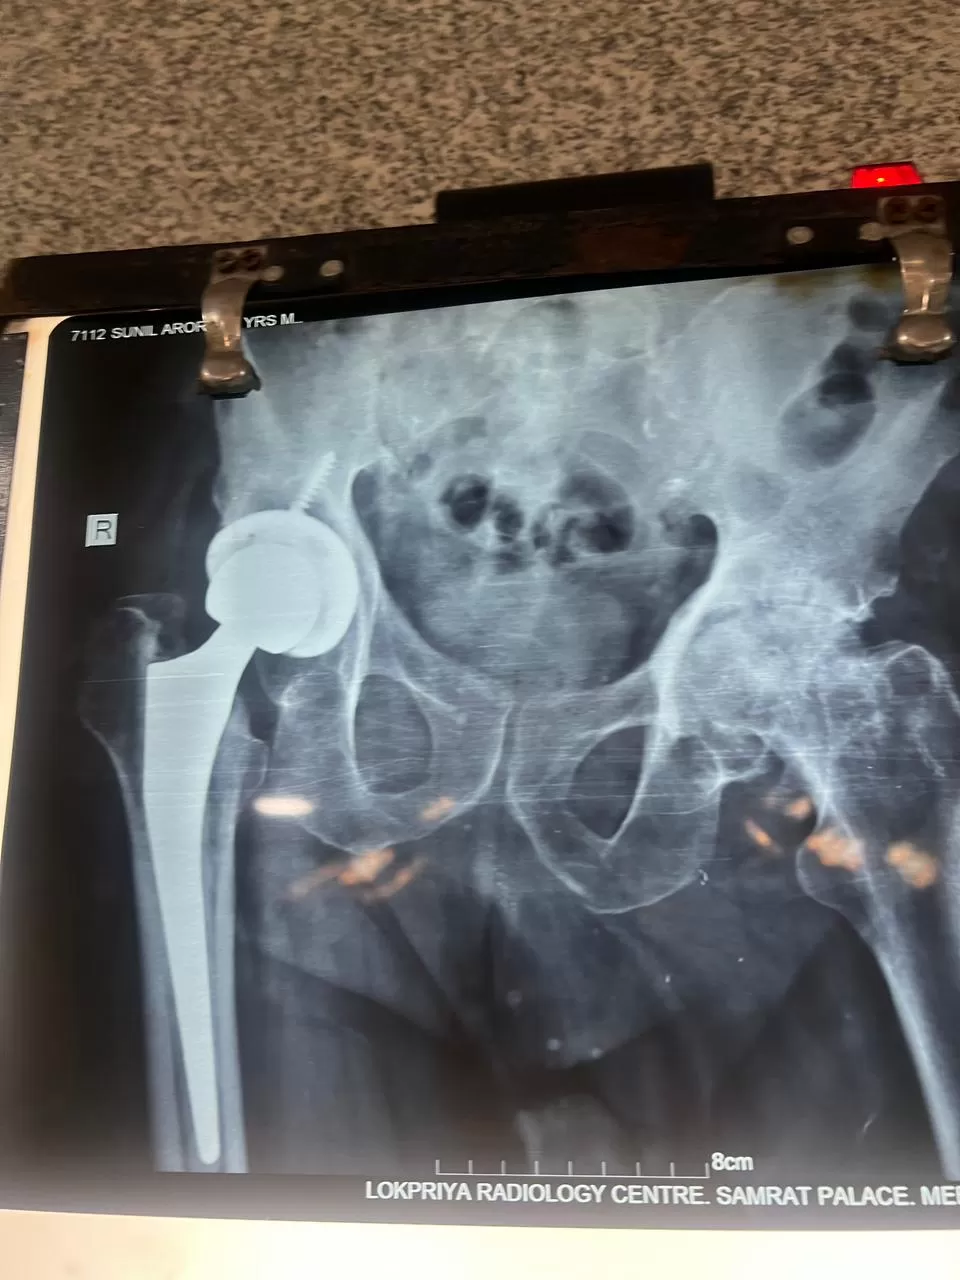

Sunil Arora

Name: Sunil Arora

Date of Operation: 19 September

Age: 66 Years